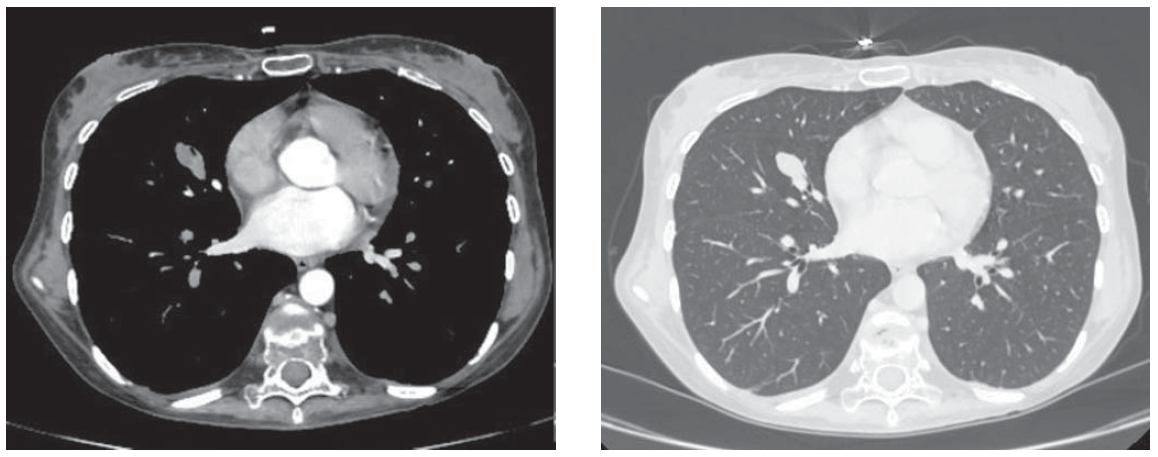

По данным МРТ головного мозга данных о наличии аденомы гипофиза не получено. В ходе дальнейшего диагностического поиска по результатам большой дексаметазоновой пробы установлен эктопический характер продукции АКТГ. При заборе крови из нижних каменистых синусов была подтверждена эктопическая продукция АКТГ. По данным МСКТ органов грудной клетки и брюшной полости с контрастированием выявлено новообразование в средней доле (S5) правого легкого неправильной округлой формы с нечеткими контурами, расположенное по ходу субсегментарного бронха, размерами 21,8 × 13 × 13 мм, неравномерно накапливающее контрастное вещество до 48 ед.Н. Медиастинальной лимфоаденопатии нет (рис. 1). При ФГДС и колоноскопии опухолевых новообразований не выявлено.

Рис. 1. МСКТ органов грудной клетки пациентки Н. с контрастным усилением.